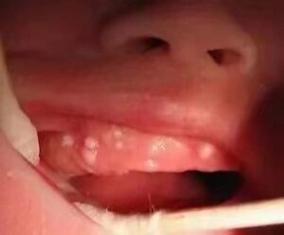

两个月宝宝口腔白点是鹅口疮吗?

最可能的原因:鹅口疮

这是两个月宝宝口腔白点最常见的原因。

- 白点像奶渍或雪花,但用棉签或湿纱布擦不掉。

- 白点周围没有明显的红肿,宝宝通常不疼也不痒。

- 白点可出现在口腔的任何部位,如舌头、上颚、内颊、牙龈等,严重时可能蔓延到咽喉部。

- 有时白点会融合成大片白色的假膜。